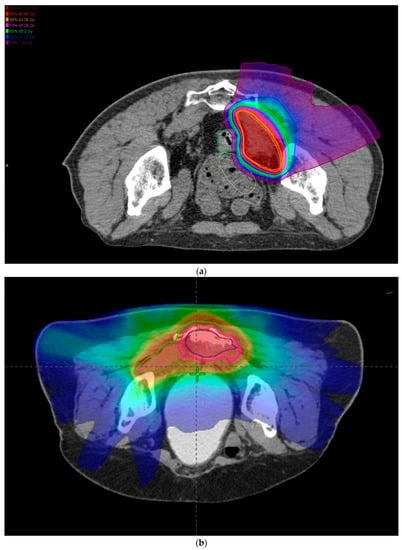

3.2. CIRT Patients

3.3. Outcomes